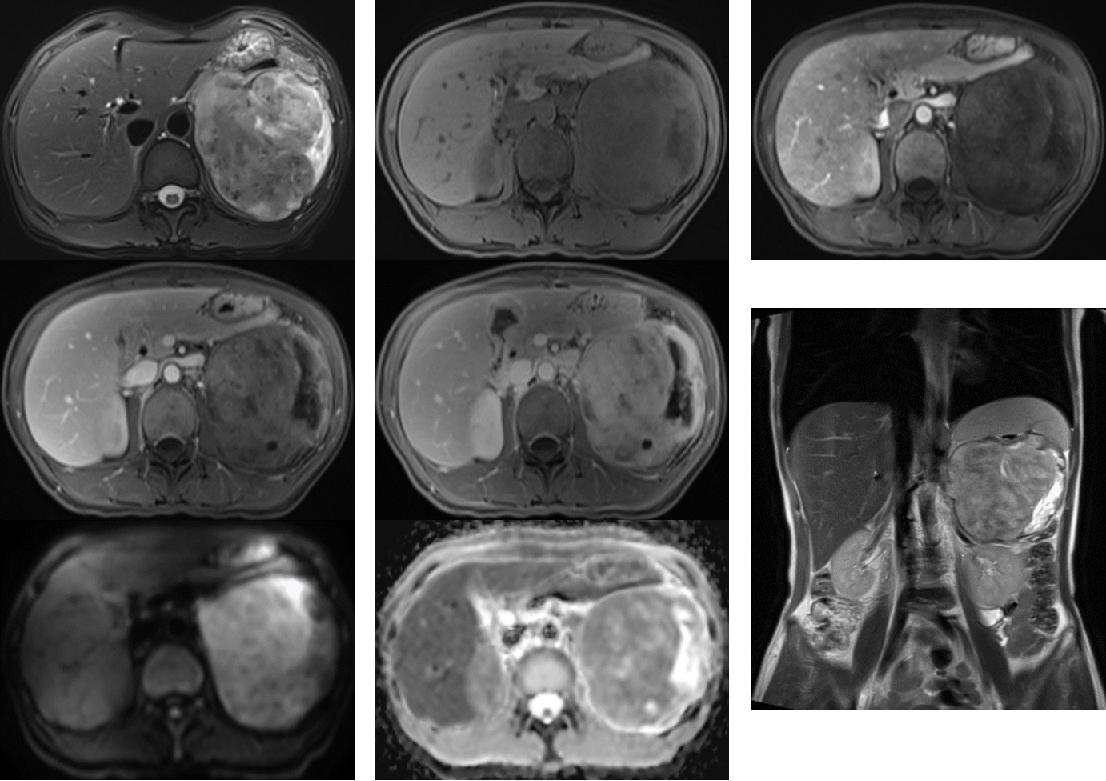

病例二

病史:女 52岁;主诉:查体发现左侧肾上腺区肿瘤3天入院

左侧腹膜后见巨大团块状异常信号灶,呈等长 T1 等长 T2 混杂信号,大小约10.0x10.5x9.6cm,边界尚清,边缘分叶,左侧肾上腺显示不清,增强扫描病灶呈渐进性不均匀强化, DWI ( b =800) 及 ADC 示明显弥散受限。胃腔及脾脏左肾受压,胃及脾静脉向前推移。右侧肾上腺、双肾未见明显异常信号及强化;腹腔及腹膜后未见明显增大淋巴结,腹腔见少许明显液体信号影。

影像诊断:左侧腹膜后占位性病变,考虑间叶源性肿瘤,恶性可能性大,建议病理学检查;

①:第一例病例梭形细胞瘤,符合间叶源性肿瘤,具体位置尚有争议,倾向腹膜内,第二例是肾上腺神经鞘瘤。